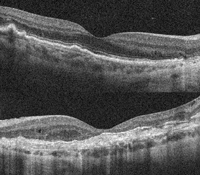

En las imágenes de OCT de ambos ojos vemos la progresión de la enfermedad a lo largo de los últimos 6 años: en el ojo derecho (

Figura 40) se ve el material viteliforme homogéneo, y que con la evolución se va produciendo la reabsorción de este material para finalmente dejar una zona de atrofia geográfica.

Al diagnóstico, el ojo izquierdo (

Figura 41) se encontraba en fase más avanzada. Puede apreciarse una TRE en el borde izquierdo de la atrofia en el estadio final de la enfermedad.

Figura 40. Distrofia viteliforme del adulto. Ojo derecho. A) Material viteliforme subfoveal homogéneo. B) Reabsorción parcial del material viteliforme. C) Atrofia geográfica tras la reabsorción completa del material.

Figura 41. Distrofia viteliforme del adulto. Ojo izquierdo. A) En el momento del diagnóstico, el ojo izquierdo se encontraba en una fase más avanzada que el derecho, mostrando reabsorción parcial del material viteliforme. B) Estructura tubular retiniana externa (TRE) en el borde izquierdo de la atrofia en el estadio final de la enfermedad. Atrofia macular grave que condiciona la hiperreflectividad por debajo de la fóvea.